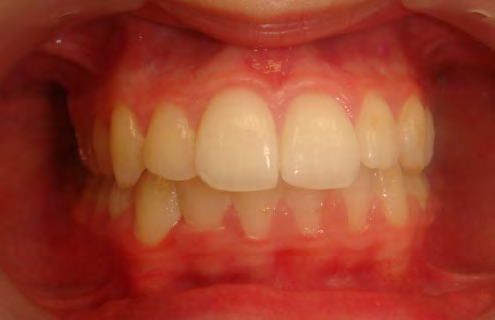

All of the patients below had been told they required extractions by orthodontists, some insisting that they could not be treated without extractions.

They were all treated without extractions, head gear or facemasks at Vakresmil and represent just a small sample of cases treated between 2004–2014.

Below are cases treated at Vakresmil without extractions within the last three years. The families had been told, “It is simply not possible for your child to be treated without extractions” by orthodontists. Judge for yourself if that was right or wrong.

The overall aim is to produce the best smile we can — a “beautiful smile”, if you will — without premolar extractions, headgear, facemasks or banded appliances. A smile that both the patient and we at Vakresmil can be proud of.